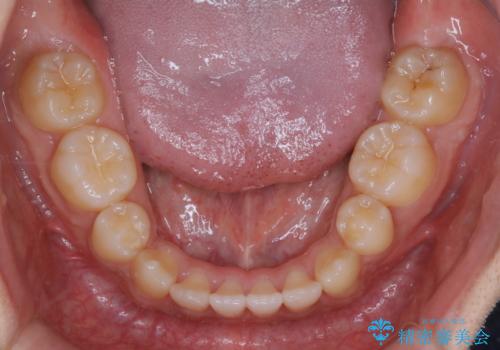

インビザライン単独でここまでできる!!抜歯矯正

1日20時間以上、正しくインビザラインを使用して頂いたおかげで、ワイヤーに切り替えることなく矯正治療を終了することが出来ました。周囲からも歯並びがすごく綺麗になったと言われたのことで大変ご満足いただけました。